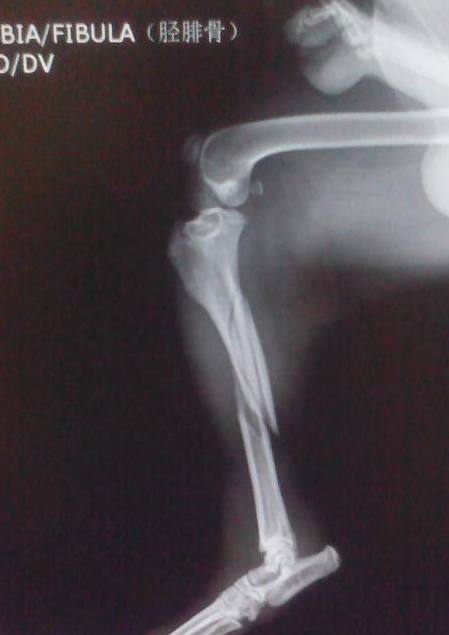

在历经医生和护士的查验以后,果真发觉狗狗的一条腿早已骨裂,而且医师提醒大家狗狗的这一条腿很有可能要截至。在网友们听见这种新闻以后宛如瓢泼大雨,大家才一瞬间搞清楚这一条狗的主人家很有可能是由于狗狗的腿从此好不上,因此才绝情的抛弃了它吧。